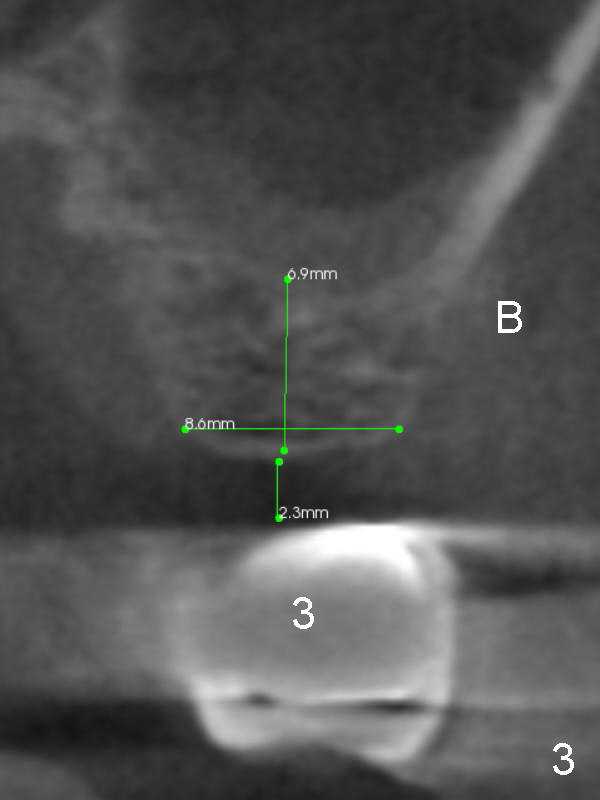

A 63-year-old man complains of loose bridge in the upper right quadrant. There is open margin at #4 (Fig.1). After sectioning between #2 and 3 without anesthesia, explore the tooth/abutment of #4 for caries. Build up or Cavit will be placed for splinted provisional with implant at #3. Use Magic Split for access and initial bone expansion, followed by Magic Expanders until 4.3 mm one. Bone density is 100-500 units. The depth starts with 7 mm and finishes with 9 mm or more from gingival margin (Fig.2). CBCT coronal section shows the bone width 8.6 mm (Fig.3). Place a 4.5x9 mm dummy implant at the gingival level for depth determination. Use a definitive implant 1-2 sizes larger (Fig.4,5). Draw blood for PRF. Also prepare Magic Lift Kit and DIO one.